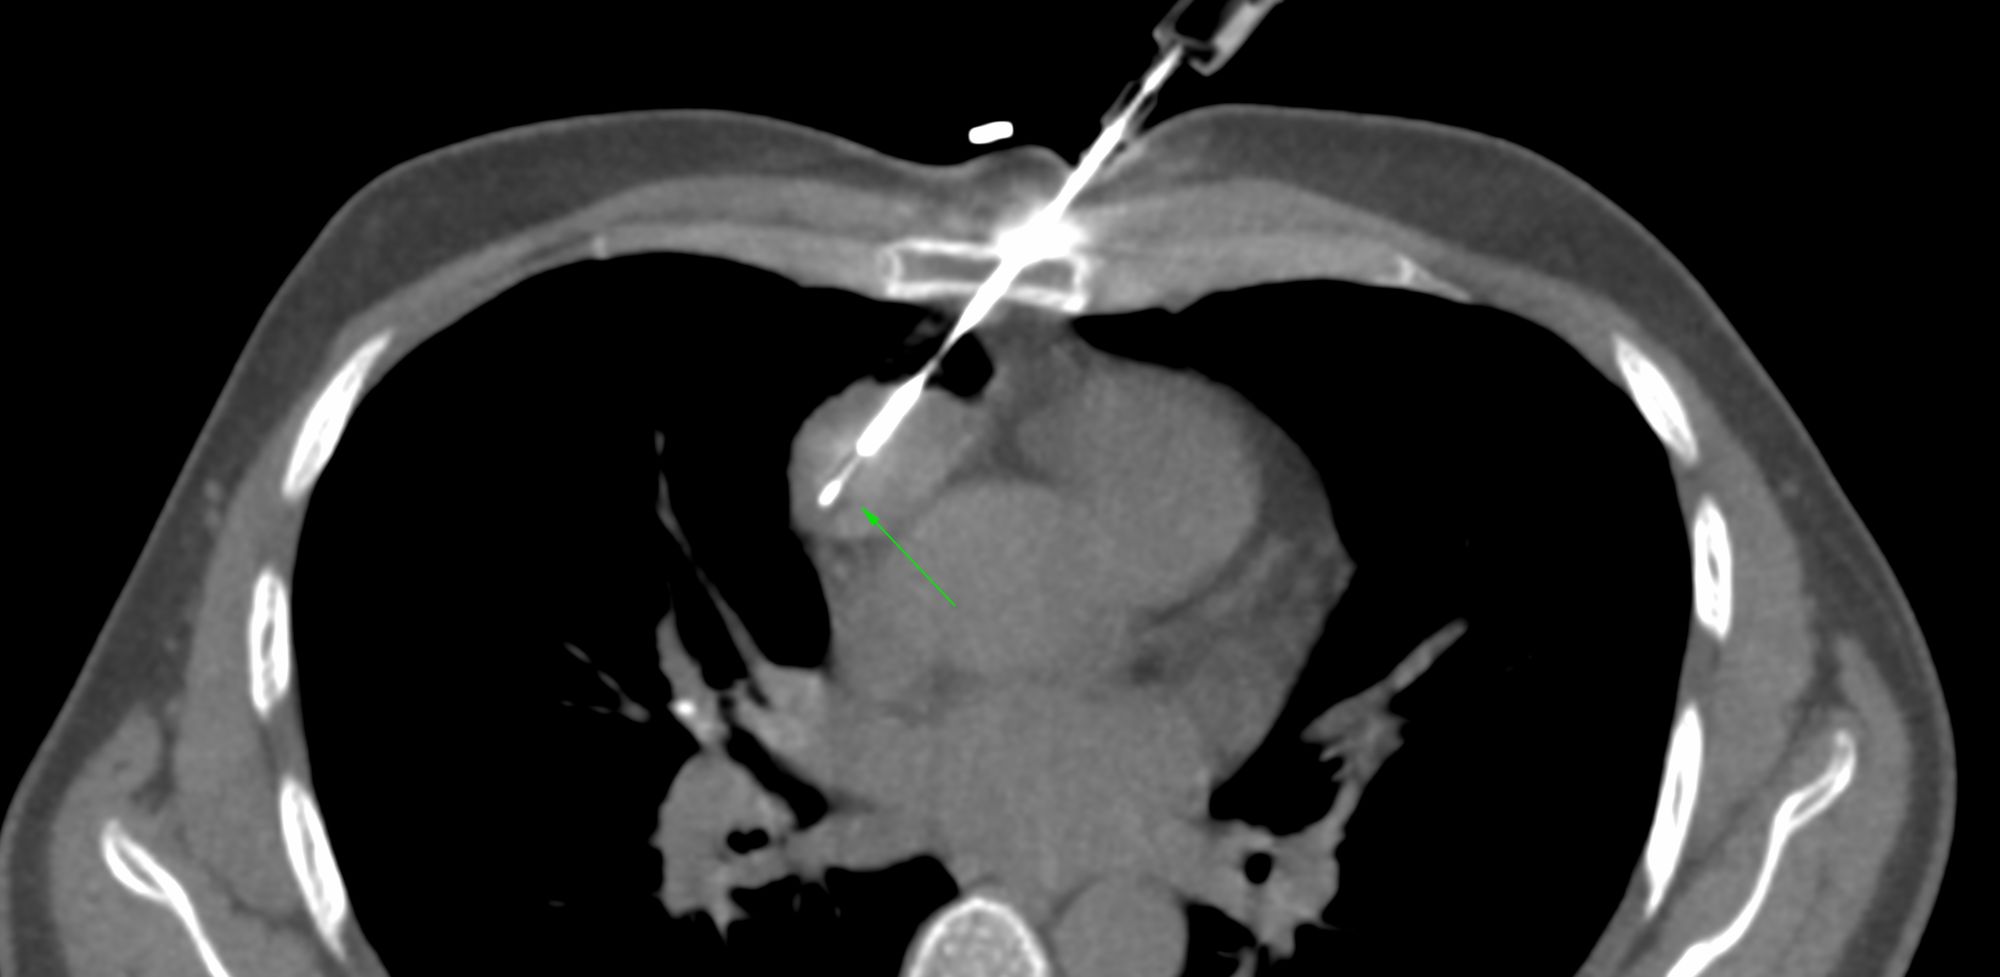

Case 69: Whose Responsibility is It After a Negative Biopsy to Push for a Repeat Biopsy?

Bhavin Jankharia - 03 December 2021